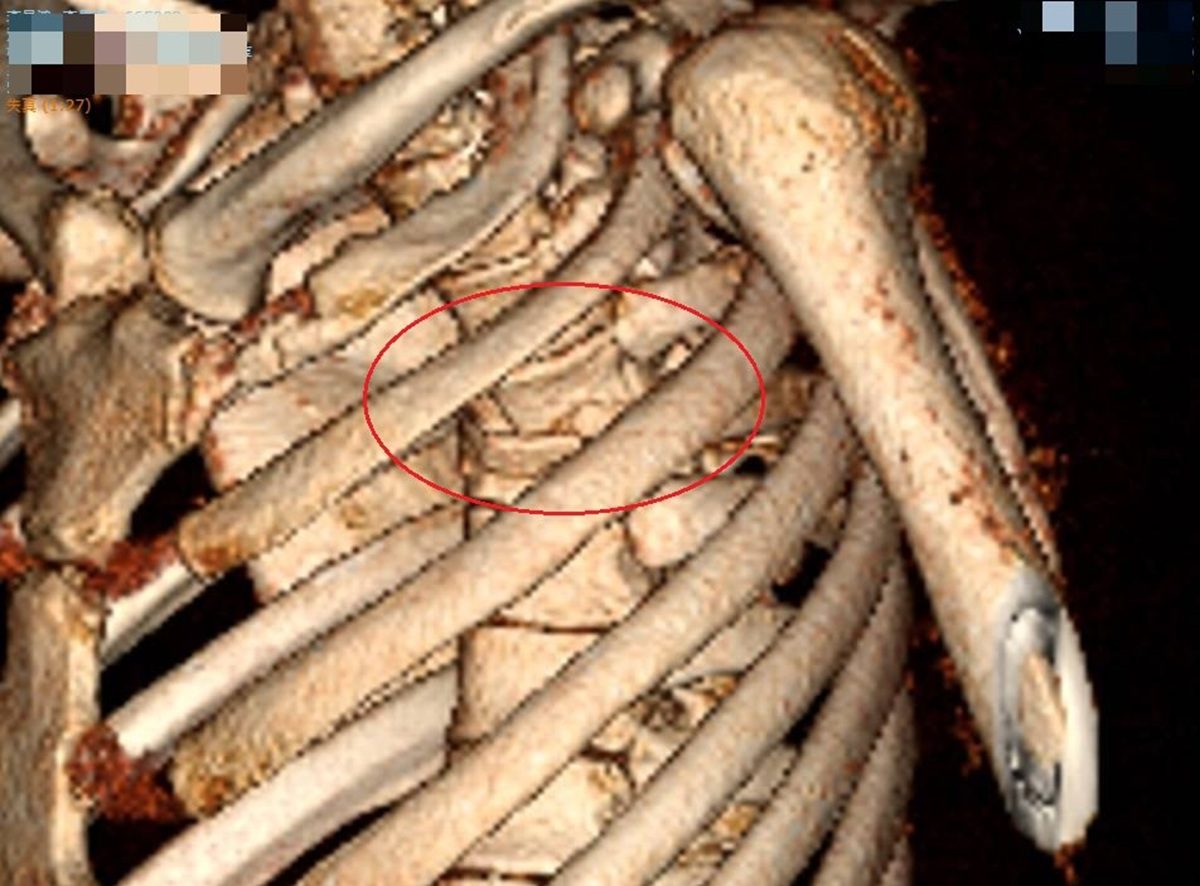

▲李先生胸部嚴重撞擊,屬於脊椎骨的胸椎第4節爆裂性骨折,壓迫到神經,雙腳無知覺,有癱瘓之虞。(圖/彰化醫院提供)

▲李先生胸部嚴重撞擊,屬於脊椎骨的胸椎第4節爆裂性骨折,壓迫到神經,雙腳無知覺,有癱瘓之虞。(圖/彰化醫院提供)

神經外科醫師張昕煥說,李先生胸部嚴重撞擊,屬於脊椎骨的胸椎第4節爆裂性骨折,壓迫到神經,雙腳無知覺,有癱瘓之虞,因此馬上手術,進行長達8小時的椎弓切除及神經減壓手術,並以10支鋼釘固定,手術順利,但李先生右腳還是不會動,肌力值0分,左腳稍微能動,肌力值2分,還是有下肢偏癱的可能。